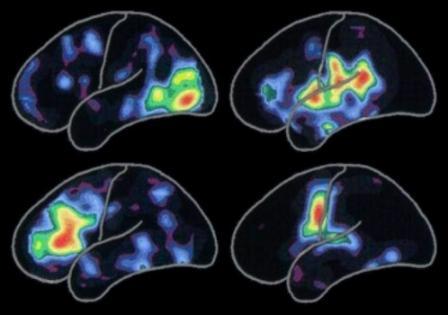

واشنطن / متابعات :حقق العلماء في جامعة كاليفورنيا في سانتا باربرا إنجازا علمياً إذ استطاعوا معرفة الطريقة التي يستخدمها الدماغ لتكوين المعلومات وترميز الذكريات.وذكر موقع ساينس دايلي أن الدراسة التي أعدّها باحثون وتمحورت حول الآلية التي يستخدمها الدماغ لذلك ونشرتها دورية «الأعصاب» قد تؤدي إلى تطوير عقاقير جديدة وفعالة لمساعدة الذين يعانون من ضعف الذاكرة.وقال الباحث كينيث أس. كوسيك، الذي شارك في إعداد الدراسة ورئيس قسم أبحاث الأعصاب في معهد بحوث الأعصاب في أميركا « عندما نتعلم أموراً جديدة ونخزن الذكريات تحدث أشياء كثيرة». وأوضح كوسيك «إن أكثر العمليات أهمية هي أن المشابك syapses، وهي عبارة عن خلايا دماغية موصولة ببعضها هي التي تجمع الذكريات في مكان واحد، ولذا يجب تقويتها ».وأضاف “ عندما تقوم بتقويتها “المشابك” فإنك بذلك تقوي الاتصالات وهذا ما يتيح لبعض هذه المشابك ترميز الذكريات”.ورأى أن “تقوية هذه المشابك مهم جداً من أجل التعلم، وجزء من هذه العملية له علاقة بخلق بروتينات جديدة تساهم في بنائها المشابك” وجعلها أكثر قوة”، مشبهاً الأمر كممارسة الرياضة والدور الذي تلعبه في تنمية العضلات. وقال “ يتعين على المشابك إنتاج المزيد من البروتينات عند تخزينها للذكريات”، موضحاً أن ذلك يحدث “عندما تكون الجزيئات التي تنقل الرسائل الجينية من نواة أخرى “ أر أن أيه” إلى باقي الخلايا ناشطة”.وأضاف “ عندما يخطر ببالك شيء ما... ربما فكرة أو شيء محفز كأن ترى شيئاً مثيراً للانتباه أو عندما تستمع للموسيقى تنشط عندها المشابك، وما يحدث بعد ذلك أمر مثير جداً للانتباه”.وقال إن معرفة البروتينات التي يحتاجها الدماغ من أجل تقوية الذاكرة وإنعاشها قد يكون مفيداً للذين يعانون من الاضطرابات في الذاكرة.